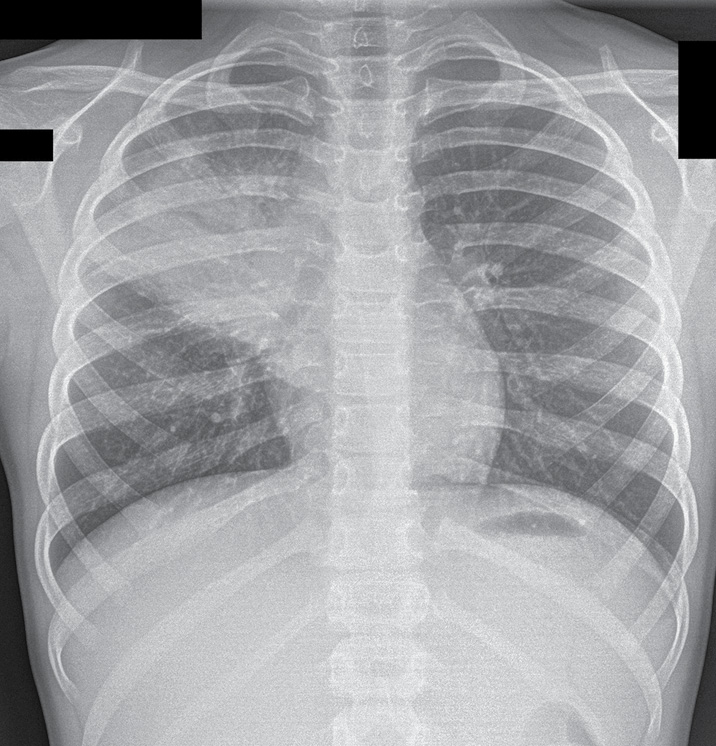

27.04 на рентгенограмме органов грудной клетки (ОГК) в двух проекциях определялось выраженное неоднородное затемнение легочной ткани по типу пневмонической инфильтрации в проекции S2–S3 справа. Легочный рисунок в зоне инфильтрации не прослеживался. Подчеркнута и подтянута кверху горизонтальная междолевая плевра. Тень сердца размыта в верхних отделах справа. Контуры диафрагмы четкие, ровные, плевральные синусы свободны (рис. 1).

Рис. 1. Рентгенограмма ребенка Н., 8 лет 7 мес., 27.04

Fig. 1. X-ray of a child N., 8 years 7 months, 27.04